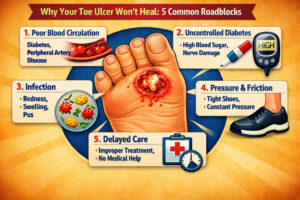

If you or someone you love has a toe ulcer that has been open for weeks — or even months...

Introduction: A Small Wound That Becomes a Big Problem You notice something on your foot. It might be a blister...

If you or someone in your family is living with a wound that refuses to heal — particularly a diabetic...